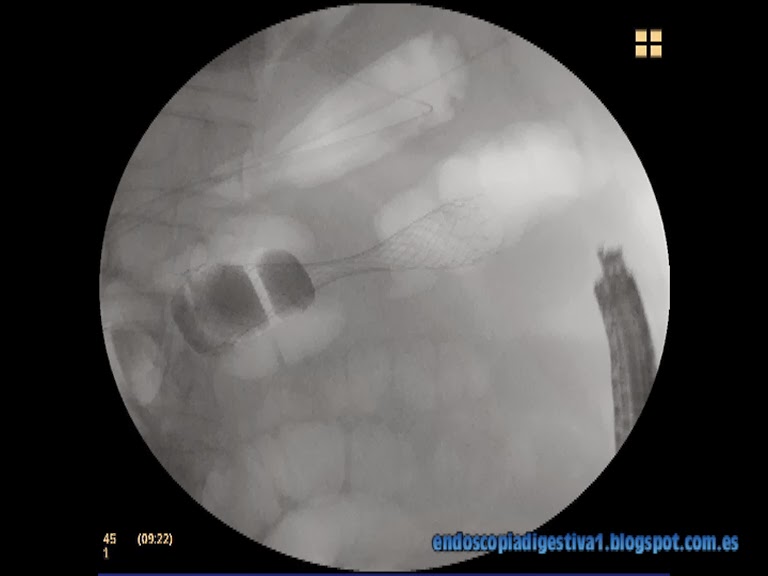

Paciente mujer de 64 años de edad con antecedentes de asma bronquial. Ingresa en urgencias por un cuadro compatible con oclusión de colon transverso acorde a la clínica y los hallazgos de la Rx de abdomen. En la exploración física junto con la analítica y Rx simple de abdomen, se descarta razonablemente una perforación. Se realiza TAC abdominal que evidencia una dilatación de colon derecho junto a asas de i. delgado junto a un engrosamiento mural corto en colon transverso, a unos 4-5 cm del ángulo esplénico. No se aprecian lesiones focales en hígado. Se decide colocar una prótesis metálica no recubierta (Wallflex 9 cm) con idea de solventar  la oclusión y poder intervenir a la paciente de forma electiva en un solo tiempo quirúrgico que cursa con éxito. La paciente es intervenida a los 10 días de su colocación por vía laparoscópica sin complicaciones.

La colocación de prótesis de colon en pacientes con oclusión aguda del colon de origen neoplásico como puente a la cirugía se ha convertido ya en una rutina en la mayor parte de hospitales. Las localizaciones habituales de colocación son el recto, el sigma y el colon descendente. No obstante, también se pueden colocar en otros partes del colon pero el riesgo de complicaciones, sobre todo la impactación de la prótesis en las paredes del colon y la perforación subsiguiente son mayores. Las localizaciones que pueden dar mayor número de problemas son el ángulo esplénico y hepático por dos razones (o en sus proximidades): la formación de bucles en el sigma que dificultan las maniobras de paso de la prótesis y su ajuste y las angulaciones que los extremos protésicos pueden formar. Este último evento puede provocar una perforación cuando la prótesis se despliega por completo y se rectifica. Por este motivo, en estas localizaciones es muy importante elegir la longitud adecuada: si la estenosis está a > 2-3 cm de un ángulo, lo mejor es elegir una prótesis corta que quede a > 1 cm de éste. Si por el contrario están mas cerca, lo mejor es elegir una mas larga que «dibuje y se extienda por todo el ángulo».